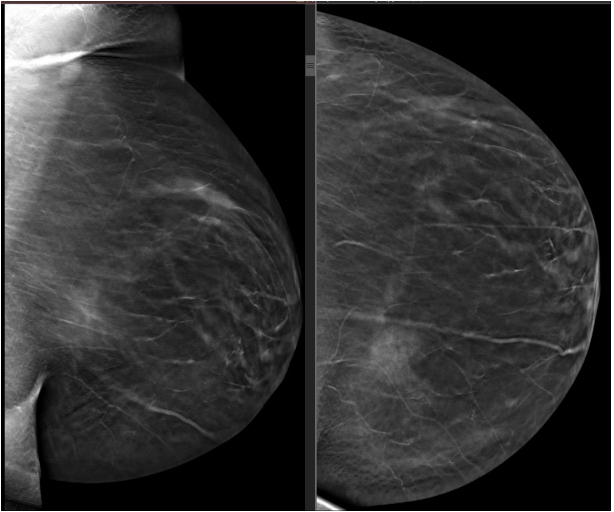

BILATERAL SCREENING 3-D MAMMOGRAM. symmetric densities observed in the posterior medial LEFT breast parenchymal margin. No mass, suspicious calcifications, architectural distortion or skin change in either breast observed.

MammoScreen®: Co-located soft tissue lesion identified in the LEFT CC and LEFT MLO views with a MammoScreen® Score of 6 supporting observation.

Opinion: LEFT breast appears to have asymmetric density of an uncertain significance. Recommendation to perform a LEFT breast ultrasound to confirm.